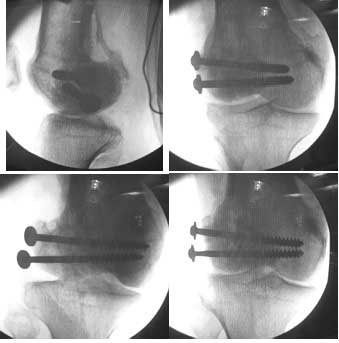

I opened it up from the lateral aspect.

Freed up the non-union site with minimal disturbance to the posterior and lateral soft tissue attachments on the lateral condyle fragment.

Applied a distractor between femoral shaft and tibia, to create a space on the lateral aspect.

This brought the lateral condylar fragment into a position that seemed to be reasonably well aligned, but showed up a bone gap.

This was fixed temporarily, bone grafted with tricortical struts, and fixed by two cancellous screws. The fragment was not large enough to afford any fixation to a plate or such implant, and the screws held it compressed well to the rest of the distal femur.

Post-op - limb is well aligned, rom 0-30, but I am not pushing that right now, for the next two or three weeks.

Further plan - hope that the screws hold the fragment appropriately till union, but if the stability on table is anything to judge by, that should not be a problem.

Pictures attached.